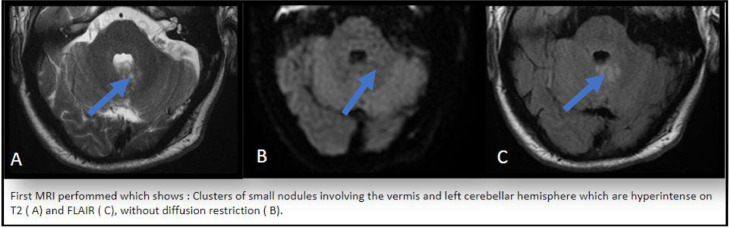

It showed left cerebellar hemisphere and vermis signal abnormalities centered on the middle cerebellar peduncle, producing a clustered nodular appearance hyperintense on T2-weighted sequences, containing small formations, frankly hyperintense on T2-weighted sequences (Fig. 1A), not cancelling on the Flair sequence (Fig. 1B), hypointense on T1-weighted, without diffusion restriction, not enhancing after injection of gadolinium (Fig. 2D), without alteration of the metabolites on spectroscopic analysis (Fig. 2E) and measuring overall 15 mm in long axis.

First MRI performed which shows: clusters of small nodules involving the vermis and left cerebellar hemisphere which are hyperintense on T2 (A) and FLAIR (C), without diffusion restriction (B).